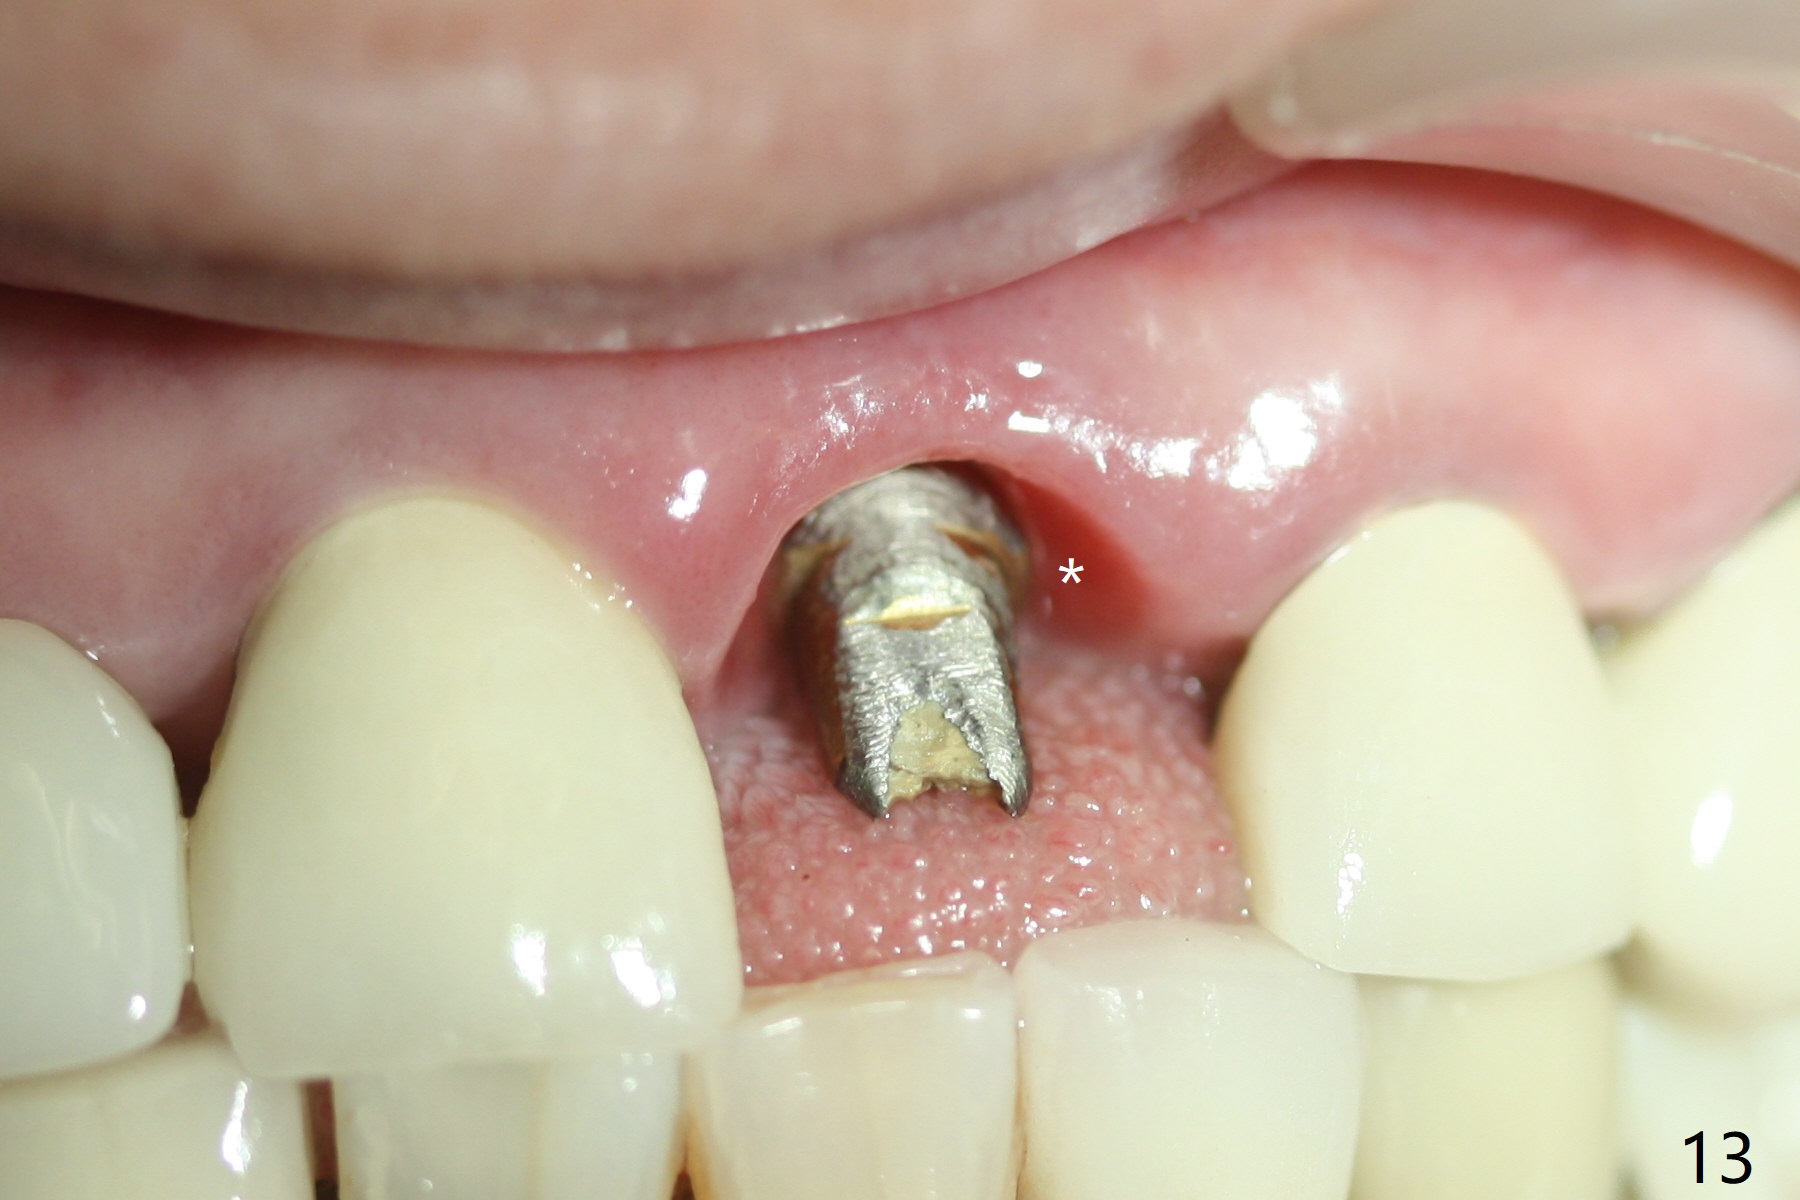

3.8x15 mm Implant with Proximity to

Nasal Floor

The buccal contour at #9 seems to be slightly concave preop (Fig.1,2 (*)). In fact the buccal plate is found to be lost when the tooth is extracted. Osteotomy is initiated as palatal as possible apical, but the occlusion dictates the coronal end of the osteotomy should be buccal, leaving the buccal gap ~ 2 mm for bone graft. The initial osteotomy (18 mm deep) appears to be close to the Incisive Foramen (Fig.3 blue dashed line). The nasal floor appears to be intact when the drill is removed. Subsequent osteotomy is adjusted so that the apical end of the osteotomy moves distal; when a 3.8x15 mm dummy implant is partially placed, there is clearance (Fig.4). It remains so when a definitive implant is seated (Fig.5); Vanilla graft is placed (Fig.5 *) before placement of a 4.5x5.5(3) mm abutment. More allograft is placed when an immediate provisional is fabricated (Fig.6 arrow and *). The gingiva remains to be recessive 1 month postop (Fig.7). It seems to be related to the bulky gingival margin of the provisional (Fig.8 *). After trimming the latter (Fig.9 *), the gingival margin immediately returns close to normal (Fig.10). The gingival margin is even between #8 and 9 two months postop, but the bone graft is exposed apically (Fig.11 ^). It may heals by itself. Otherwise debridement, regraft, PRF and suture are pending. The coronal portion of the socket heals 4 months postop (Fig.12). The gingival cuff forms by the immediate provisional (which is removed for impression) 4 months postop (Fig.13 *). While the full Zirconia crown at #7 remains intact (Fig.14), the PFM at #9 has porcelain chip (Fig.15). It is partially due to the occlusion; while the crown at #7 has clearance with the opposing dentition (Fig.16 *), the one at #9 has no. The access hole at #9 (Fig.17 *) seems to weaken the crown structure. There is no access hole at #7. No solid posterior support is another contributing factor for chip (Fig.18). The buccal plate has mild atrophy at #7 and 9 (Fig.19 *). A piece of bone graft is being expelled apically at #9 (Fig.20 >) and is removed subsequently (Fig.21). Before impression for repacking porcelain, the opposing incisal edge has been shortened (Fig.22 arrows, as compared to Fig.16). Since the ideal access hole is at the incisal edge (Fig.25 black circle), buccal to the existing one (Fig.24 A), the abutment is torqued before the repaired crown is recemented (Fig.23). Finally the crown has occlusal clearance (Fig.26). Porcelain chips again around the access hole of PFM 1.5 years post 2nd cementation. The dense bone at the crest (*) cannot explain why the abutment is not loose, since it remains incompletely seated (>). As it was trimmed short, an angled abutment is used (Fig.28). The coronal end is lingual, while #9/24 is edge to edge. The lingual aspect of the coronal end of the abutment is heavily trimmed to reduce bulkiness. To prevent chip, Zirconium crown will be fabricated in spite of the fact that it does not match the PFM of #8 (potential shade discrepancy). The patient is pleased with the new Zirconia crown (Fig.29).